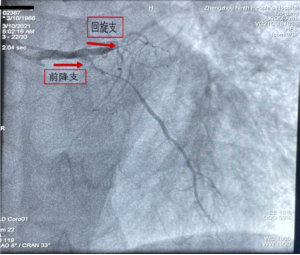

3月10日03:37分,当大家还在睡梦中时,一名55岁男性患者到达郑州市第九人民医院急诊科就诊。到院时患者持续性胸闷,难以忍受,追问病史已有症状数天。急诊科考虑患者急性心肌梗死立即联系胸痛中心并与家属沟通后单绕CCU后将病人送入了导管室。患者造影显示:冠心病、三支血管病变、前降支近中段80-90%狭窄、第一对角支完全闭塞、回旋支99%弥漫性狭窄、右冠全程弥漫性病变、左室后支完全闭塞。血管病变极其严重,心功能极差(LVEF21%),病死率极高,但心血管介入中心团队依然冒着风险在赵明中主任指导下,由CCU杜明远、张超医师完成了这台高危手术。

图:患者造影结果